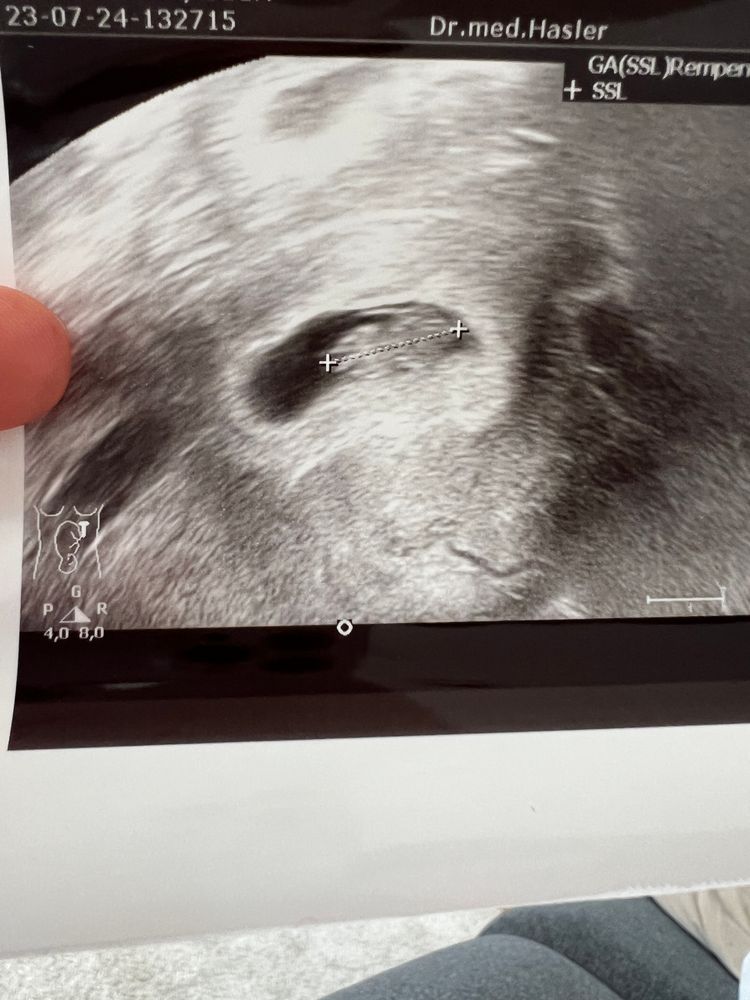

Гематома 3х1 см на девятой неделе

На фото гематома слева от ПЯ.